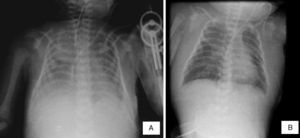

2Imagenología (Dra. María Teresa Valadez)En las últimas radiografías se observó borramiento de los ángulos costodiafragmáticos, opacidad en pulmón izquierdo y engrosamiento de los tejidos blandos (Figura 1A). No se puede descartar zona de consolidación. Se puede observar el edema de tejidos blandos de manera difusa hasta cuello y un infiltrado pulmonar sugerente de edema pulmonar agudo (Figura 1B).